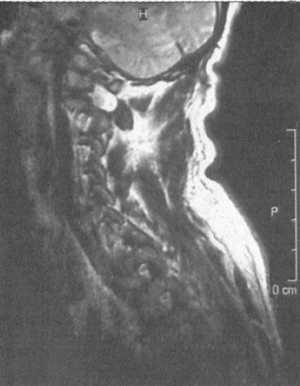

Ценную информацию о состоянии вывихнутых позвонков и спинного мозга дает

МРТ (рис. 2.6, 2.7). МРТ позволяет определить наличие зон ишемии в спинном

мозге (рис. 2.8, 2.9), состояние ликвородинамики (рис. 2.10).

Рис. 2.7. Переломо-вывих скользящий C6-C7 позвонков с компрессией

спинного мозга на данном уровне